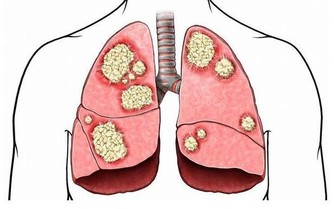

▼原來這個症狀被稱做「乾性溺水」,當水快吸進肺部時,身體會出現保護機制,

造成喉痙攣,導致呼吸能力受影響及昏迷、疲憊、咳嗽及胸口疼痛等。

這樣的症狀發生時,不一定是大量的水才會造成,

有時候只是微量的水就會導致危險發生,即使一開始反應正常,

但一小時之內就有可能因為水進入肺部而導致死亡。